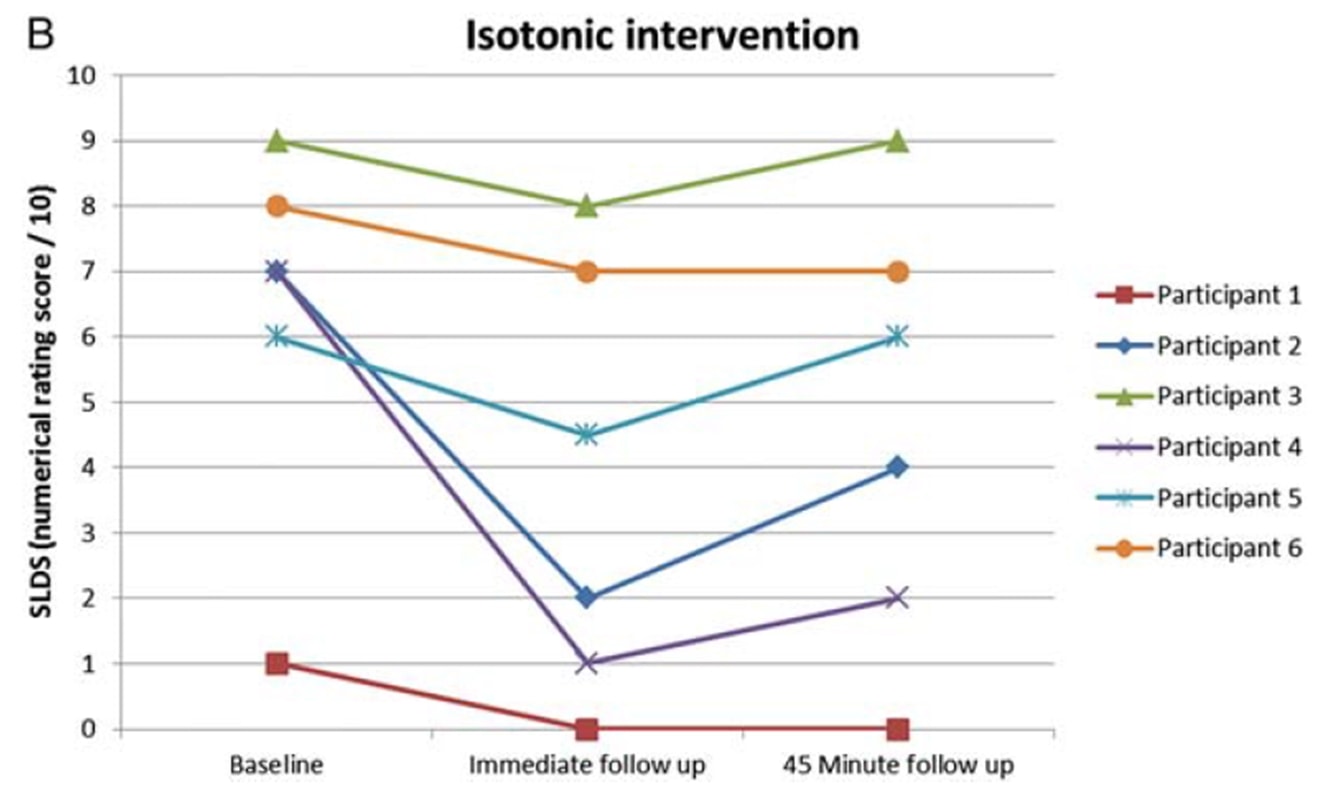

Rio et al. (2015) hanno avviato una tendenza quando hanno condotto uno studio cross-over su 6 giocatori di pallavolo con tendinopatia rotulea. I risultati sono stati sorprendenti: tutti i giocatori hanno registrato un'immediata diminuzione del dolore, passando da una media di 7/10 sull'NRS a 0, e solo uno dei 6 giocatori ha riportato un dolore residuo di 1 per almeno 45 minuti dopo le contrazioni isometriche. Il protocollo utilizzato era di 5 serie con 45 secondi di contrazione in una macchina per l'estensione delle gambe e uno sforzo pari al 70% dello sforzo volontario massimo. Hanno anche scoperto che l'isometria era in grado di ridurre l'inibizione corticale e di aumentare la forza del 19%. Hanno confrontato l'intervento isometrico con un intervento isotonico e gli effetti osservati nel gruppo isometrico non sono stati raggiunti nel gruppo isotonico:

Gli stessi autori hanno condotto uno studio di follow-up sulla stagione con atleti saltatori due anni dopo (Rio et al. 2017) in cui hanno confrontato un programma isometrico e uno isotonico. In questo studio i risultati sono stati un po' più eterogenei in entrambi i gruppi, con una maggiore riduzione immediata del dolore nel gruppo isometrico: